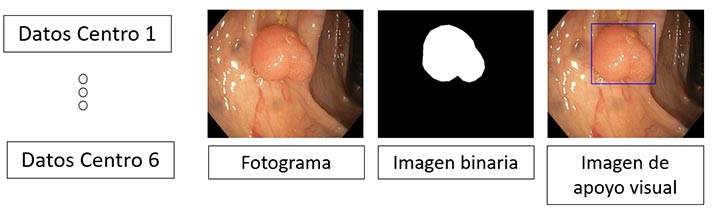

La IA apoya la detección de pólipos realizada mediante una colposcopía

Los modelos de IA son entrenados para la detección con imágenes de casos reales para su comparación

“Nosotros alimentamos la IA con una base de datos de imágenes vasta y la entrenamos, se dice que es un aprendizaje supervisado porque primero el médico va calificando como lesión de bajo grado, de alto grado o una infección, y a partir de ese etiquetado aprende a relacionar nuevos casos, se crea un modelo matemático y a partir de esto desarrollamos sistemas de apoyo a la toma de decisiones del experto, nunca consideramos sustituirlo, es más bien darle herramientas para que tenga una segunda opinión o facilitar que haya un experto artificial en lugares donde el humano no pueda tener un fácil acceso”, agregó el entrevistado.

En la actualidad han comenzado un nuevo proyecto, enfocado en la detección de pólipos colorrectales, dado que el cáncer colorrectal es la segunda causa de muerte a nivel mundial entre hombres.

“La forma en la que se hace la detección es a través de un colonoscopio, una cámara que se introduce en el colon; no obstante, aproximadamente un 20% de los pólipos no se detectan, entonces consideramos que, si se tiene un sistema de apoyo, es como un segundo ojo que está viendo la misma imagen”.

El investigador puntualizó que la idea es detectar a tiempo los diversos tipos de pólipos y determinar si son malignos o benignos, aplicando las técnicas de visión por computadora, específicamente en el área de imagenología médica.